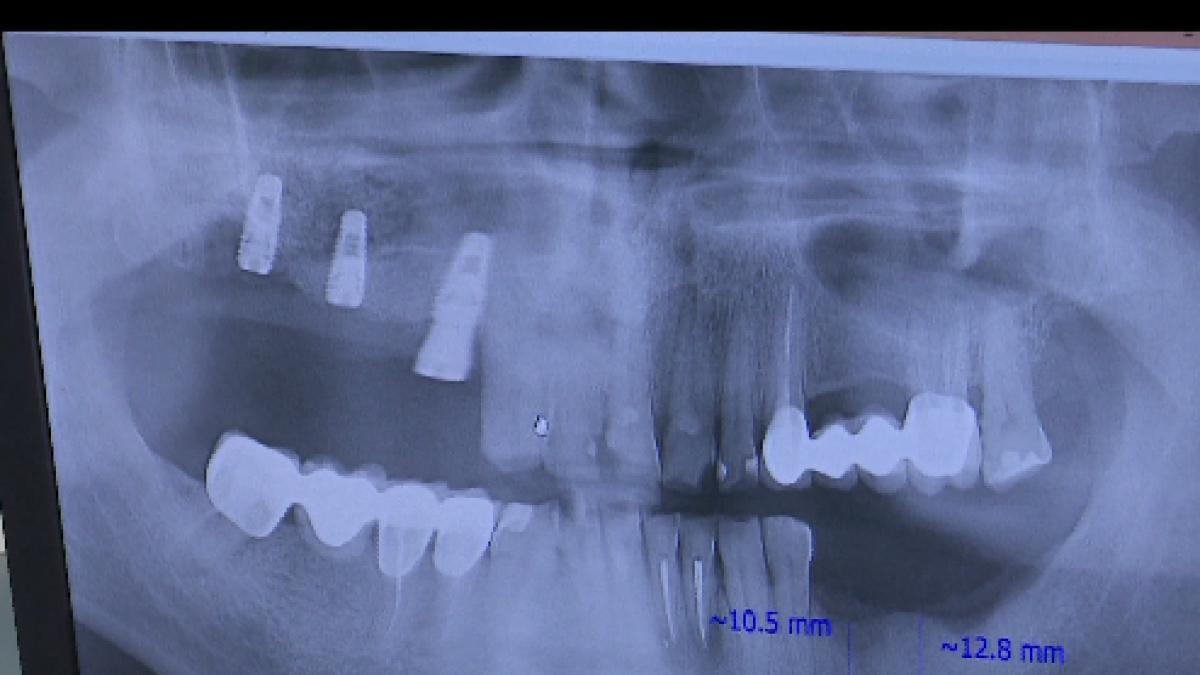

Această nouă facilitate este certificată de două proceduri stomatologice care acționează sinergic: o nouă tehnologie de implant si o procedură de vindecare rapidă. Recuperarea are la bază componente ale sângelui pacientului și anulează multe dintre problematicile postoperatorii ale implanturilor dentare.

Implant dentar, gata într-o zi